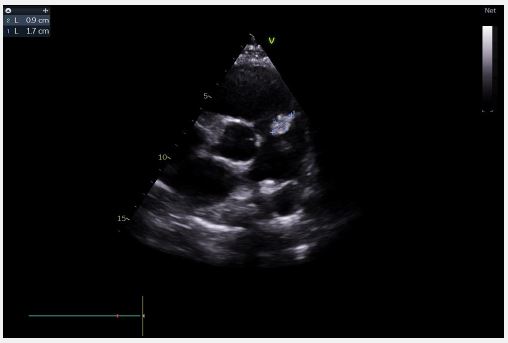

Echocardiography revealed a restrictive PDA with a 6-mm diameter and a significant gradient, along with mobile vegetation attached to the pulmonary valve leaflets and the origin of the pulmonary artery (Figure 1), leading to severe pulmonary insufficiency. The mitral valve was calcified with a vegetation measuring 11×7 mm, and mild mitral regurgitation was noted. The Left Ventricle (LV) was dilated with reduced ejection fraction (Figure 2). The Right Ventricle (RV) was non-dilated with preserved systolic function. The Inferior Vena Cava (IVC) was slightly dilated but compliant. Extension investigations found no septic emboli.

Image is Not Display Check it

Figure 1: Mobile vegetation attached to the pulmonary valve leaflets.